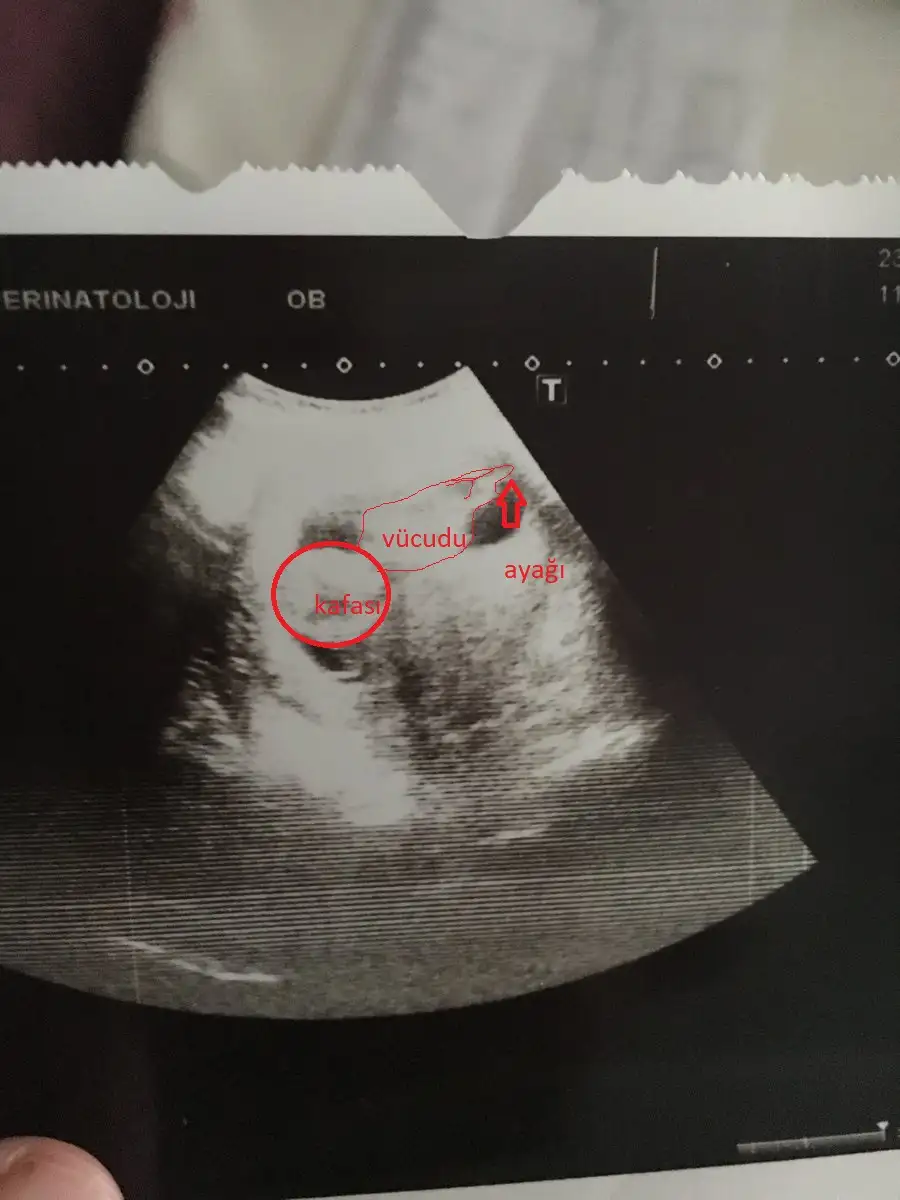

görülüyormuşum sevindim evet küçük biraz ben kafasını bile anlayamadım

Aynen bende öyleyim daha servikal yetmezlik le alakalı yazmıştım yine kimse görmedi şimdi resimle geldim yine tık yok insan doktor sonrası nasıl mutlu mutlu yazıyor cvp alamayınca tuhaf oluyor